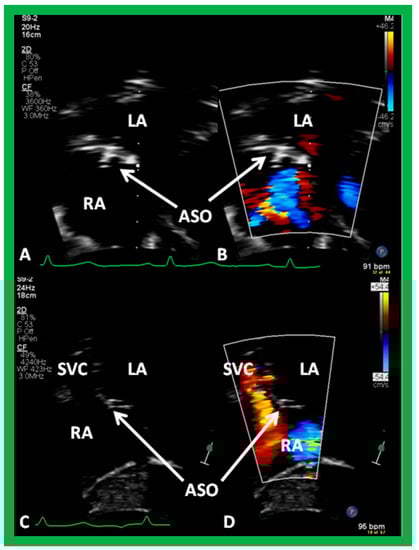

8.1. Amplatzer Septal Occluder

9.2. Device Position